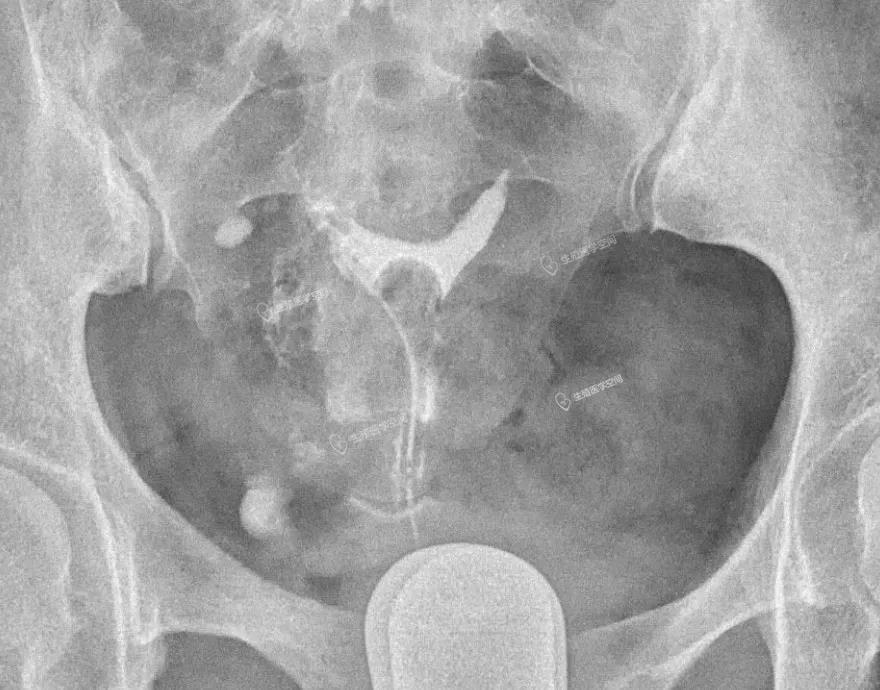

病例2 女 32岁 继发不孕,子宫输卵管造影发现双侧输卵管峡部阻塞,为峡部结节性输卵管炎(SIN)所致输卵管闭塞,不管是宫腹腔镜或放射科的介入再通术都疏通不成功。男方检查均正常。于是做试管婴儿。足月顺产一健康婴儿。